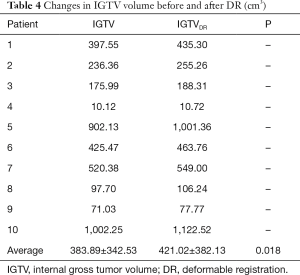

Comparison of IGTVs before and after DR

The IGTV before DR was 383.89±342.53 cm3, with a 9.67% increase observed following DR (421.02±382.13 cm3), indicating that a significant increase in IGTV volume occurred after DR (P=0.018) (as shown in Table 4).

To assess the accuracy of image registration, we adopted three indicators: overlap degree of the liver, the displacement of the bifurcation point in the portal vein and celiac axis. Our results demonstrated that maximal displacement occurred in the cranial to caudal direction, in keeping with previously published reports (12,13). We used DR technology to analyze the application of 4DCT and MRI images in the delineation of the liver target. Our results revealed that the delineation of GTV size and range based on MRI is significantly greater than 4DCT images. GTV increased by an average of 4.23% (P<0.05) and IGTV volume increased by an average of 9.67% (P<0.05), suggesting that MRI may be a good supplement to CT image information. This not only improves the accuracy of HCC target identification using 4DCT but also may be beneficial in cases where there is a lot of exit noise on the original 4DCT image and failure to identify tumor boundaries.